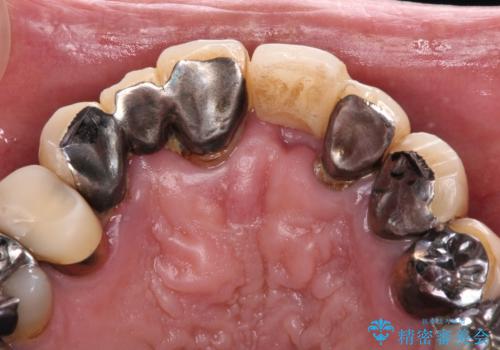

転倒で折れてしまった前歯 インプラントによるオールセラミックブリッジ治療

- 転倒により前歯3本が折れてしまったとのことで、インプラントによる治療を希望して来院された患者様です。

既に近医で真ん中の歯1本は抜歯されており、その隣の2本も破折していると言われたとのことでした。

診断をした結果、前医の診断の通り、2本とも破折しており、既に抜去している歯を含めて3本の抜歯が必要な状態でした。

抜歯する歯の両隣も治療が必要と思える歯であったため、広範囲なオールセラミックブリッジによる治療も提案しましたが、患者様本人の希望もあってインプラント2本による欠損部のみのブリッジ治療を行うこととしました。

治療により前歯は非常に安定しましたが、インプラント部の両隣、特に反対側の前歯はクラウンのやり直しが必要な状態であったので、今後反対側の治療も実施していく予定です。